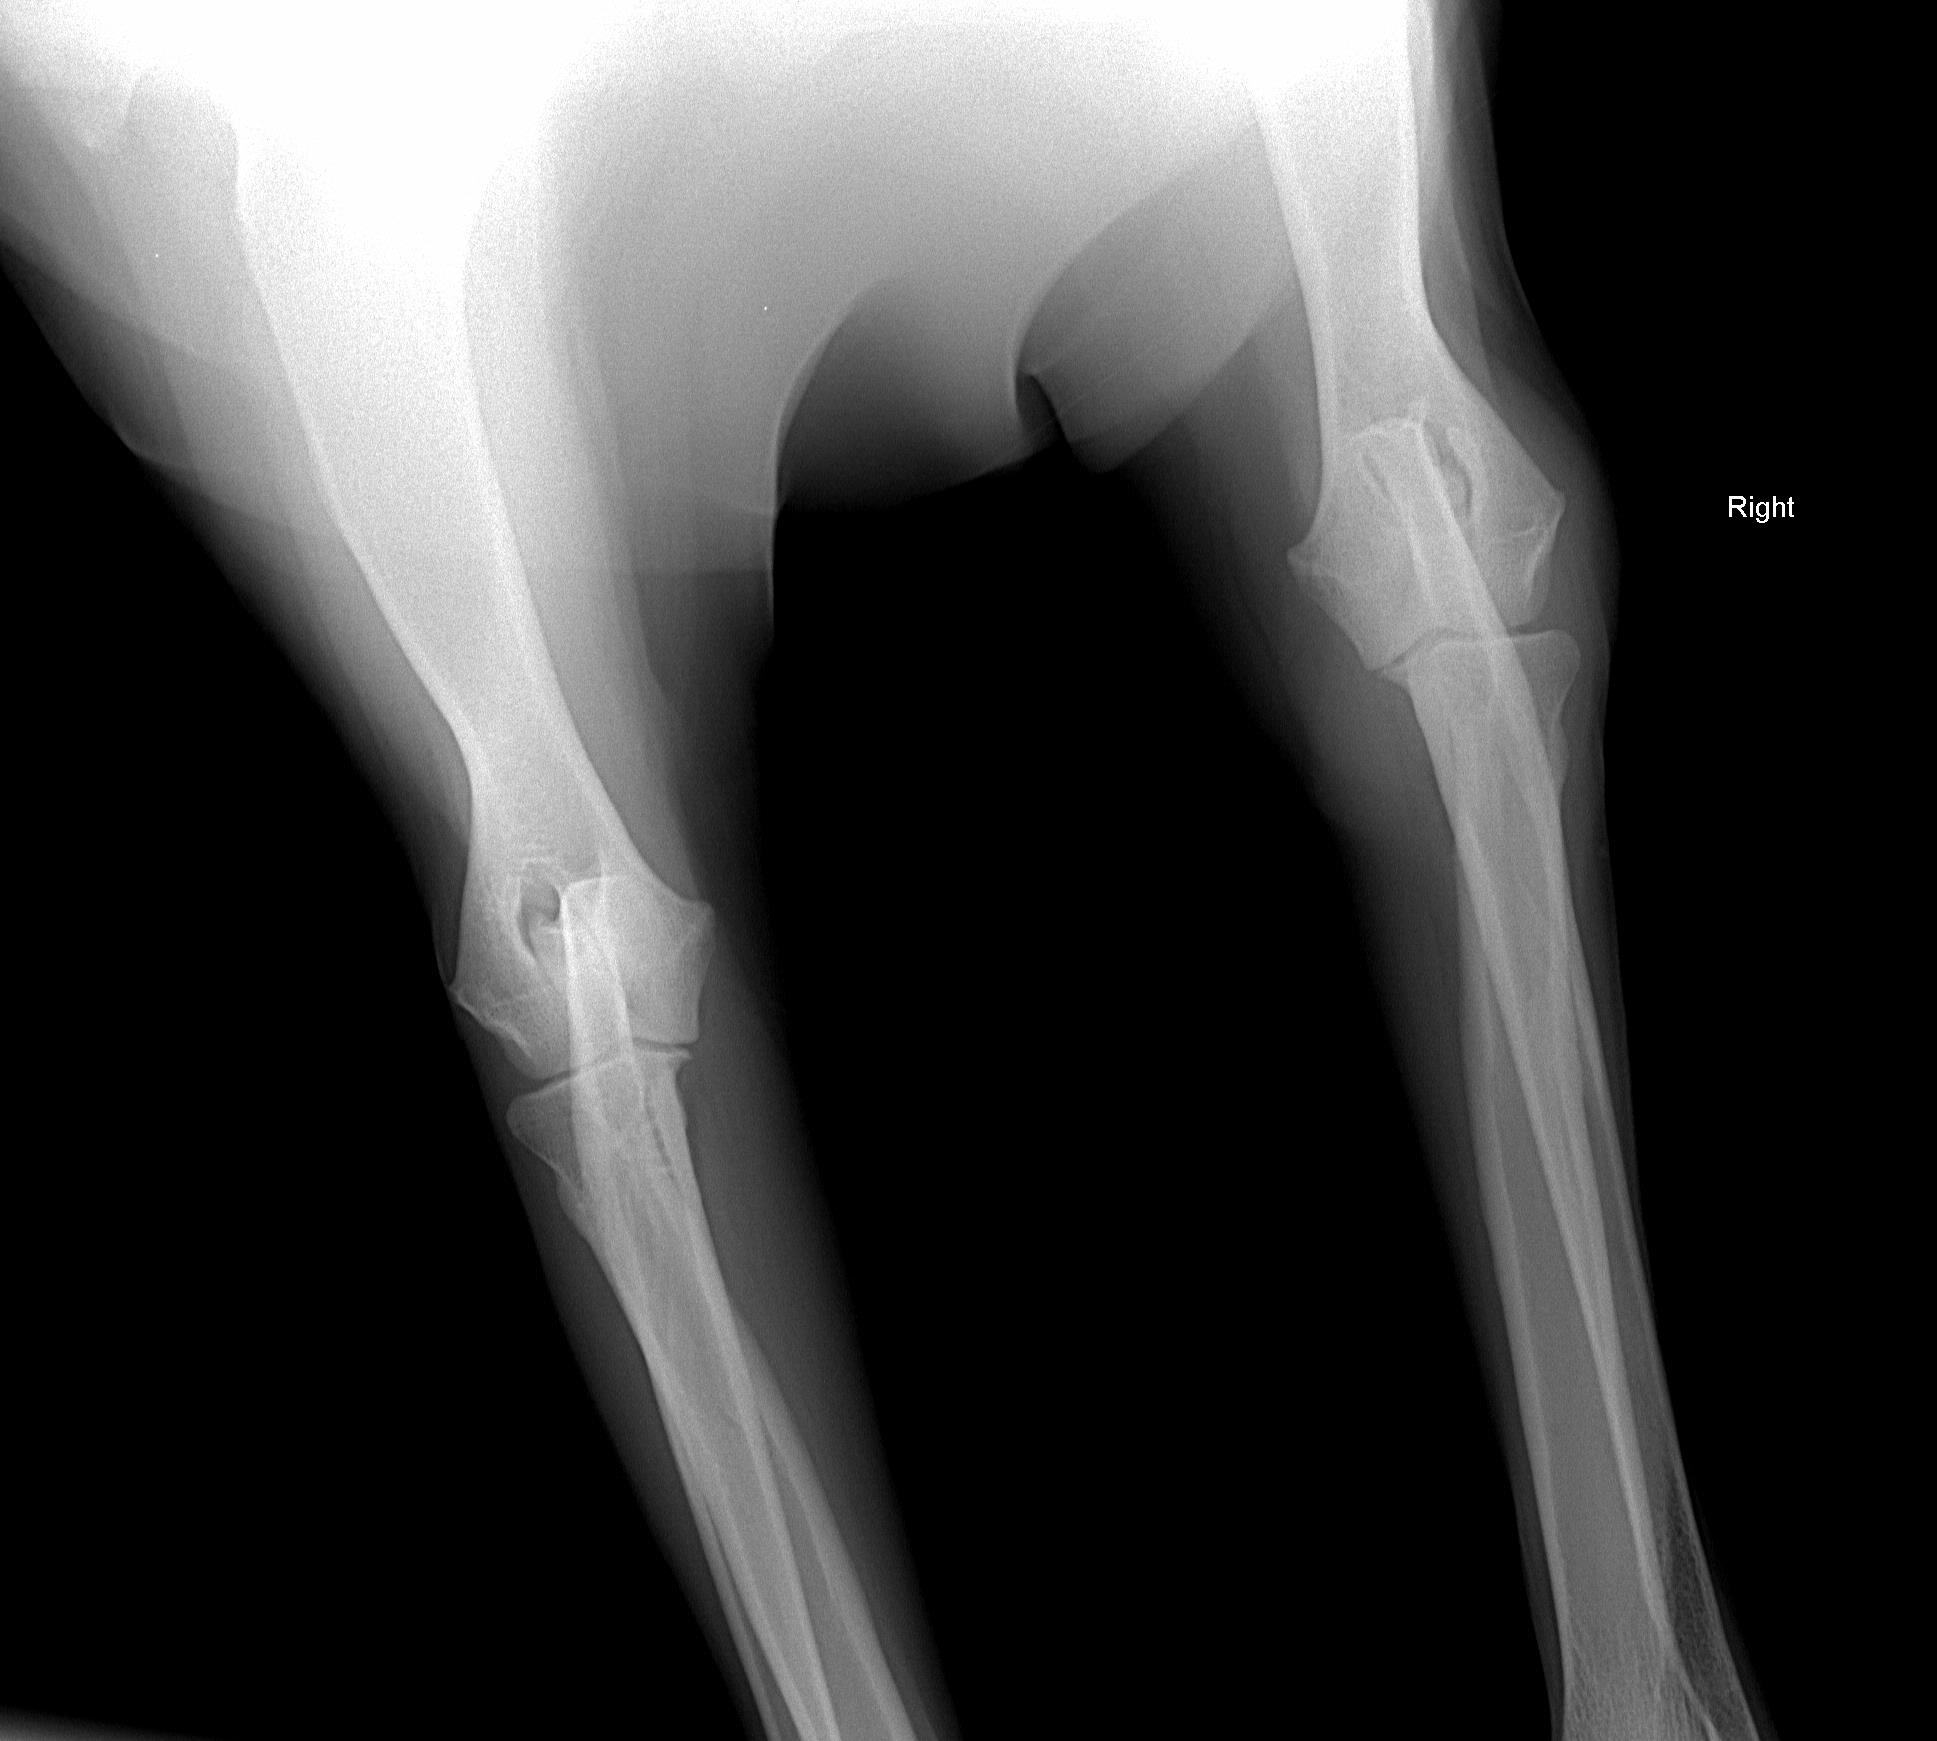

August 1, 2008 - X-rays taken at AMVC in Audubon, IA by Dr. Kristin Longfellow. She was not sedated for the x-rays. She was in slight discomfort in the area of the elbow if pressure was applied, at times seeing her trying to put weight on her toes, she was not in distress, but stiff and sore. We increased her metacam up to her weight limit.

August 4, 2008, Zoey was miserable, reluctance to go down two steps; favoring her front leg; licking it; swelling around elbow; very limited movement, etc. The swelling on the right elbow is not warm, nor cold to touch (unchanged). The swelling is hard/solid. Zoey was sleeping on her blanket (orthoped bed) on the floor without attempting to get on the bed with us at night. Zoey's eyes said she was miserable even though she was trying not to show it. The right leg is clearly marked on the xrays. She was conscious and not sedated for the xrays.

Zoey seen August 1, 2008 by Dr. Kristin Longfellow

due to limping and swelling of the front right forearm/elbow/shoulder area.

X-rays below.

On July 3, 2008, after Zoey finished her pig ear she was chasing her tail and caught the corner of the wall and never recovered from her injuries.The xray was taken 2/13/09

The following xrays were taken August 2008.